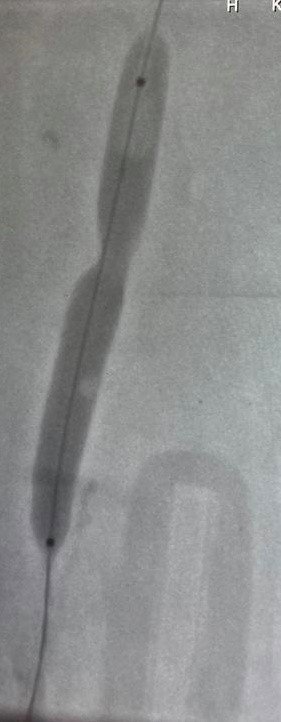

KEAH Kalp Damar Cerrahisi Bölümü A.B.D. Öğretim Üyesi Dr. Burak Tamtekin ve ekibi, 77 yaşında yaşlı bir hastanın bacakta oluşan pıhtının önce kalbe, daha sonra akciğere atması sonucu hayati tehlikesi oluşabilecek hastaya, herhangi bir kesi yapılmadan, narkoz verilmeden, anjiyo yöntemi ile risksiz bir şekilde, toplardamarda oluşan pıhtı çıkarma işlemi yaptı.

Ameliyatsız yöntemle ilk kez böyle bir operasyon yapıldığını söyleyen Tamtekin, "İleri derecede bacağının şiş ve yürüyemez bir halde hastanemize gelen 77 yaşındaki Hakan amcanın bacağının şiş ve yürüyemez bir durumda olduğunu gördük. Yaptığımız ilk muayenesinde bacak toplardamarlarında oluşan pıhtıları gördük. Bacakta oluşan pıhtıları çıkarmak için öncelikle karın içine bir filtre yerleştirildik. Daha sonra pıhtı dolu damarın içine girip, bacakta biriken pıhtıları özel bir aygıtla parçalayıp dışarı çıkardık. Narkoz verilmeden anjiyo yöntemiyle yaptığımız bu başarılı operasyonla akciğere pıhtı atmasını da bu uyguladığımız yöntemle önlenmiş olduk. Kastamonu'da ilk kez yapılan bir buçuk saat süren anjiyo uygulaması sırasında Hakan amcayla hoş sohbette bulunduk. Ekip olarak biz işimizi yaparken, oda bize Kastamonu'nun güzelliklerini anlattı. Anjiyo sonrası Hakan amcamızı servise aldık. Bacaktaki şişi inemeye başladı. Operasyondan 1-2 gün içinde rahatça kalkıp kendisi yürüyebilir hale geldi. Yürüyemez durumda geldiği hastanemizden, sağlığına kavuşup, bizlere dua ederek, hastanemizden yürüyerek taburcu olan Hakan amcamıza Kalp Damar Cerrahisi ekibi olarak, sağlıklı ömürler dileyerek, hastanemizden taburcu ettik. Bu tür ameliyatlar Kastamonu Eğitim ve Araştırma Hastanemizde ileri merkezlere gidilmeden yapıldığını Kastamonu'nun kadirşinas insanlarına bu vesileyle ayrıca hatırlatmak isteriz" dedi.